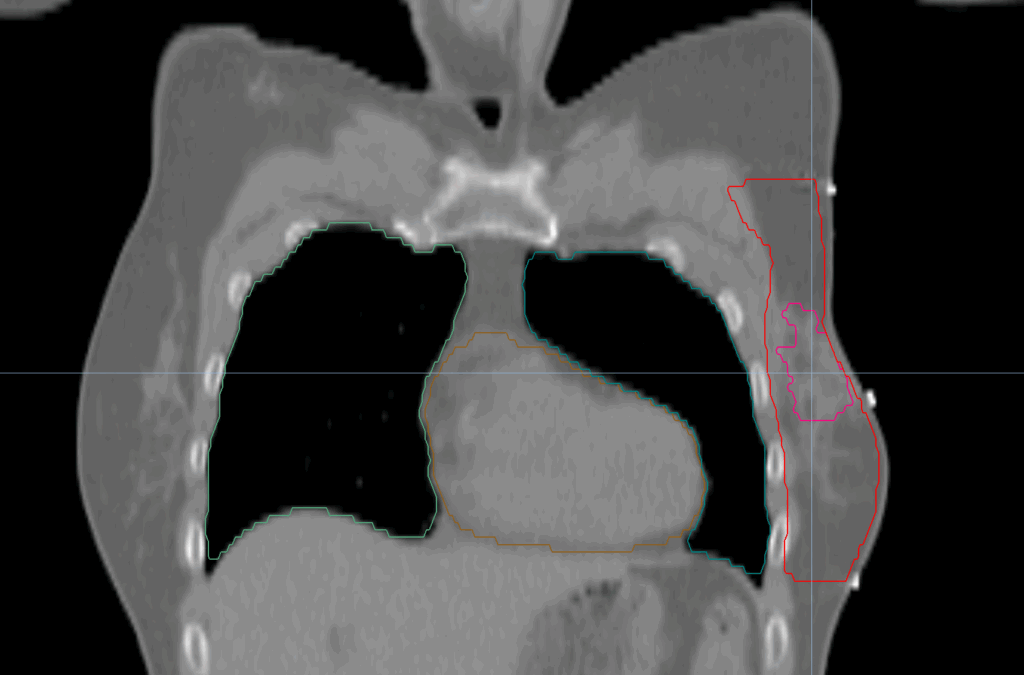

Planning CT Images

PTV(s) Volume, Length

617 cc, 18 cm